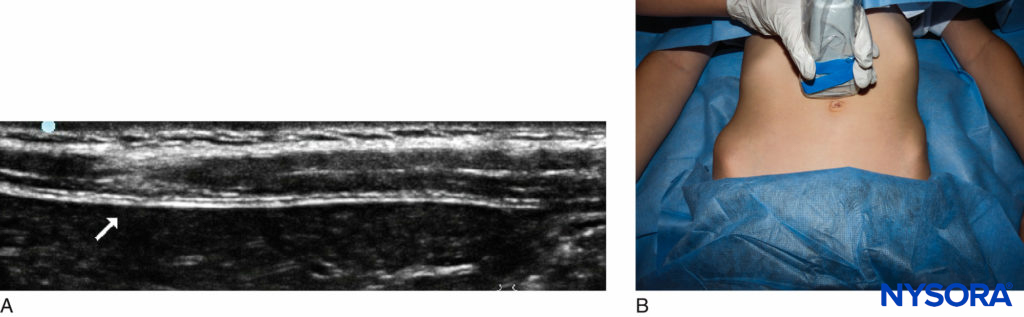

Ultrasound-Guided Technique A linear probe suffices in all but the largest adolescent. Applying probe pressure improves the US image, as this brings the sciatic nerve closer to the probe (Figure 6). Visualizing the nerve may be difficult in arthrogrypotic children, in whom it may be obscured by fibrosis. Where there is difficulty identifying the nerve, a longitudinal scan from medial to lateral and back may be attempted, looking for a band of hyperechogenicity (Figure 7). Once the sciatic nerve identified, rotate the probe back into the transverse plane. Alternatively, track down distally to the popliteal fossa, and identify the nerve before retracing your steps. With US, it is often possible to see the posterior cutaneous branch of the thigh, medial and superficial to the sciatic nerve, and it is important to ensure the local anesthetic covers it. An in-plane technique is advisable for single injections, whereas an out-of-plane technique is often better for catheter placement. When placing catheters, first inject one-third of the available local anesthetic by the lateral aspect of the nerve; the remaining two-thirds is used medially to make space for the catheter. This technique ensures the nerve is surrounded.

FIGURE 6. Probe position and sonoanatomy at the subgluteal level

FIGURE 7. Longitudinal scan of the thigh highlighting the sciatic nerve in a 6-year-old.